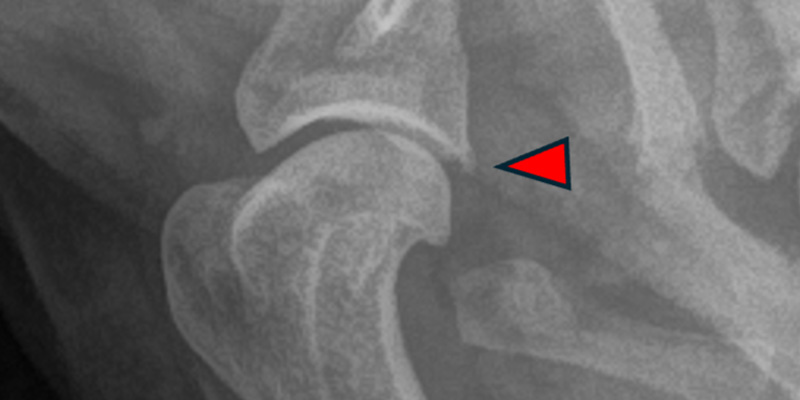

In October 2023, Martha started limping on her left forelimb. As a 10-year-old, it was likely that osteoarthritis was the cause. It was recommended that Martha started a joint supplement and NSAIDs were discussed, which the owners facilitated. However, in November Martha deteriorated and was not weightbearing properly on that limb at all. Upon examination, it was thought there could be some nerve pain so further analgesia was added (Gabapentin and NSAID combination). The owner requested further investigation, so our orthopaedic experts worked Martha up, gaining enough evidence that there was ground to radiograph and take samples from the left shoulder joint. It was identified that a mild osteophyte (bone spur) of the caudal glenoid (the socket of the ball-and-socket shoulder joint) was present.

Radiograph of affected shoulder with osteophyte highlighted